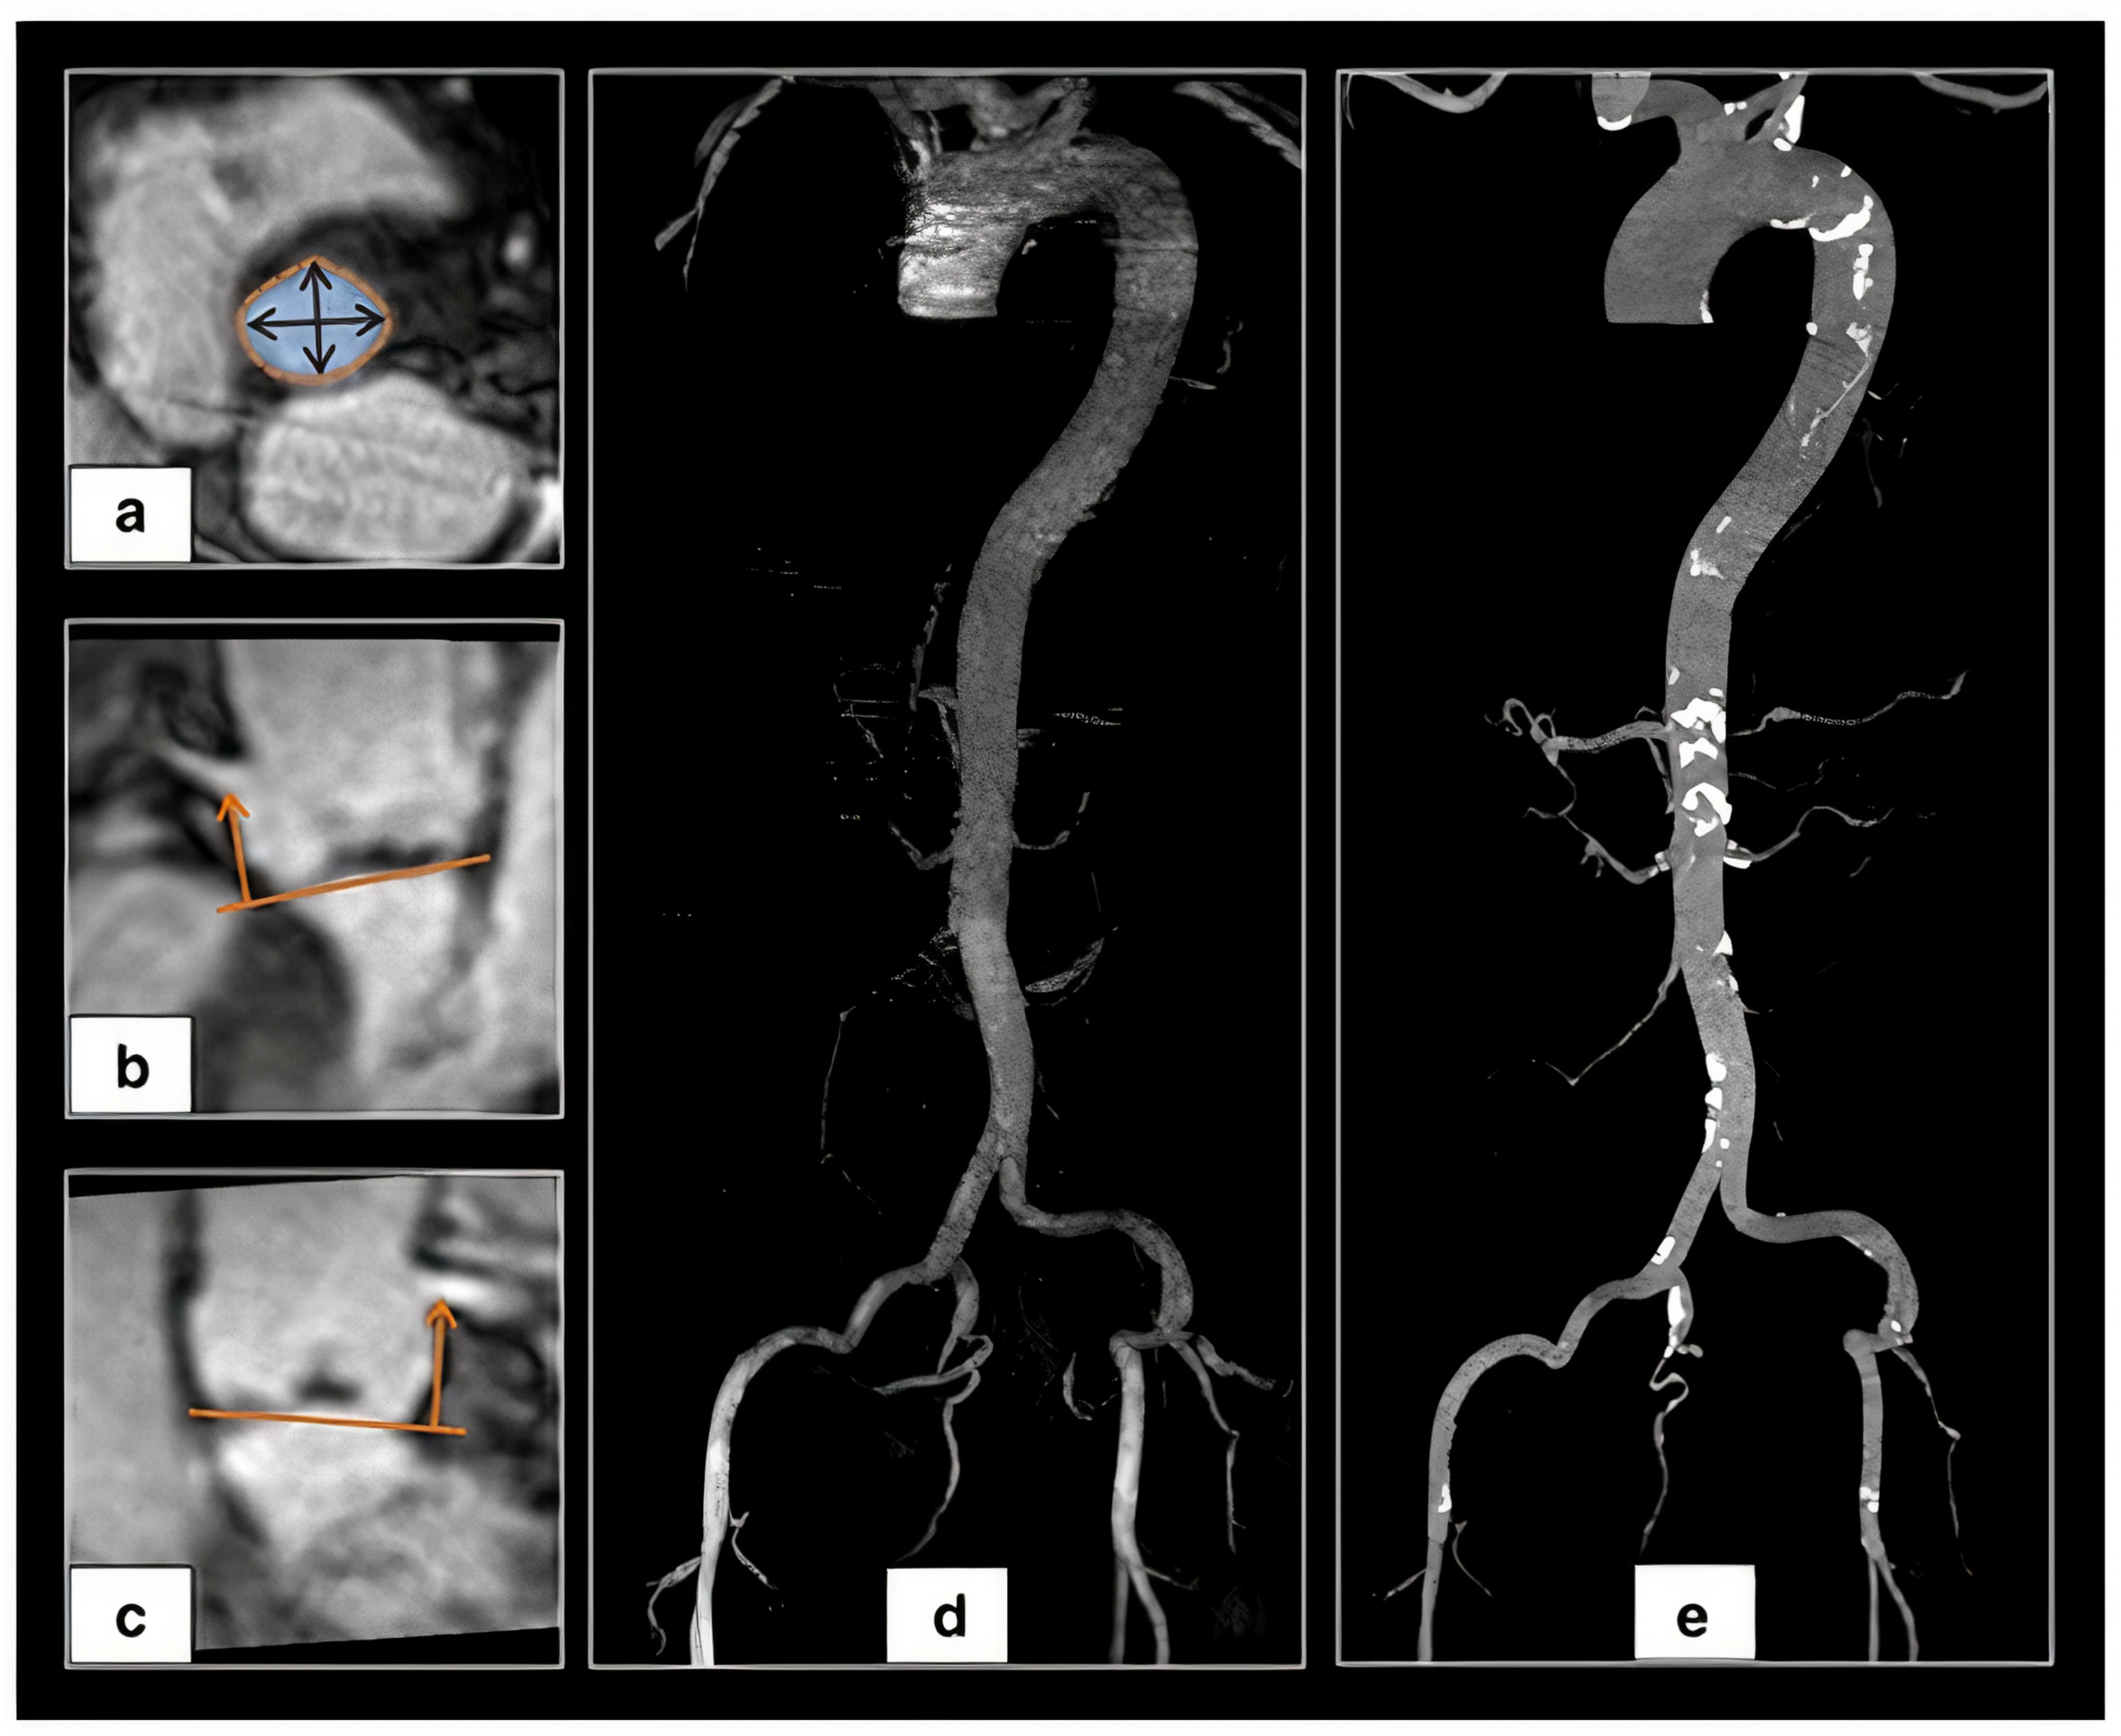

2.7. Peripheral Access Vessels

3.2. Available Methods

3.2.1. Manual Sizing

3.2.2. Semi-Automated and Automated Sizing